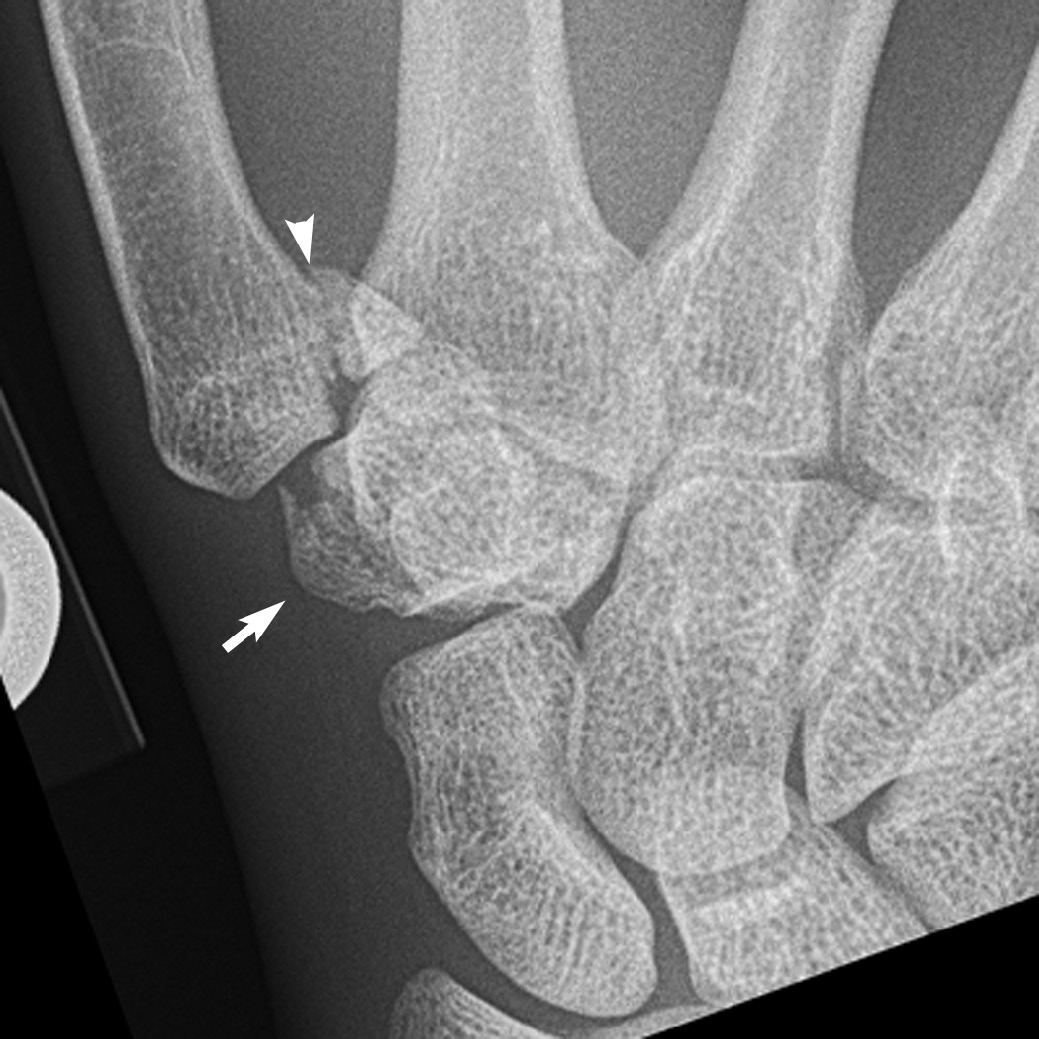

Anatomical classification of scaphoid fracture:

1. Proximal pole fracture (20%).

2. Waist fracture (70%),

3. Distal body fracture (10%).

4. Tuberosity fracture,

5. Osteochondral fracture.